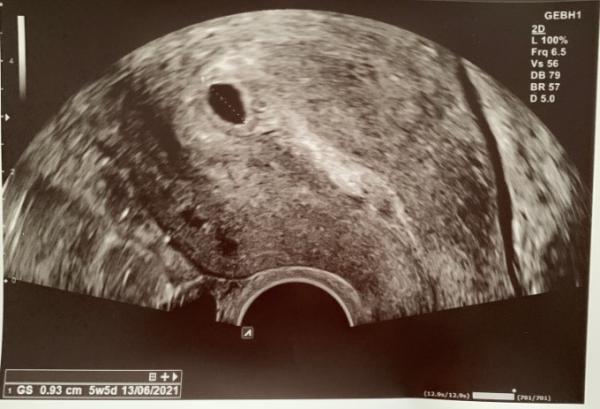

Ich war gerade beim Arzt und man sah nur eine leere Fruchthöhle. Bei wenn war das auch so ? Ist das normal ? Ich bin 5+1 Und ich musste so früh zum Arzt weil er in Urlaub geht und mich gerne vorher sehen wollte.

Bei dem Bild steht 5 W 5 Tag oder habe ich einen Sehfehler? Bei mir war bei 5+0 auch nur die Fruchthöhle zu sehen.

Wenn man genau hinsieht sieht man, dass die fruchthöhle ausgemessen wurde. Der ermittelte Durchmesser der FH würde zu 5+5 passen. Das heißt aber weni. an der größte der fruchthöhle lässt sich schlecht ein schwangerschafstalter bestimmen